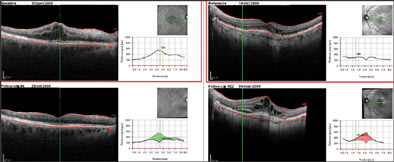

In both cases, atrophy of the retina, as identified on OCT, explains the better visualization of subretinal structures. In particular, choroidal vessels are evident and their limits are sharper than under normal retina areas; even sclera could be visualized under choroidal vessels. Note that, along the scan line, there is an area of hypertrophic RPE area corresponding in retinal imaging to 1 of the residual autofluorescent zones surrounded by atrophy. In Figure 4, a comparison is shown between SD-OCT (top panel) and TD-OCT (bottom panel) images of the right eye. Best-corrected VA in this eye was 20/32 because of a relatively conserved neuroretina in the foveal region. The retina is diffusely thinned so that choroid and choriocapillaris are visible. Note the high backscattering (*) in correspondence of an atrophy area: In SD-OCT imaging, choroidal vessels are more distinguishable than in TD-OCT images.

Figure 4. Dry AMD analyzed with SD-OCT (top panel) and TD-OCT (bottom panel). General thinning of retina explains the good visualization of choroid. Note the area of atrophy with high backscattering (*). Analysis of RPE condition in this area is only possible using SD-OCT, while TD-OCT does not permit distinguishing this layer from the choriocapillaris and choroid.